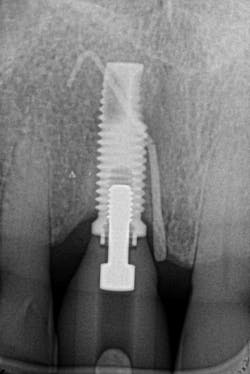

Figures 25 and 26: One-year postsurgery. Clinically all signs of retrograde peri-implantitis have been eliminated and radiographic bone fill can be seen.